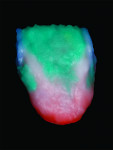

On the palatal side of the restoration, the incisal one-half was covered with a thin layer of MM yellow to provide a warm appearance to the restoration (Figure 18 and Figure 19). Dentin D2 was then layered over the gingival one-half, and marginal ridges were formed (Figure 20) to cover the incisal over the dentin (Figure 21). The first firing of the restoration was carried out with firing temperatures following the manufacturer’s recommendations (Figure 22).

After firing, a thin strip of enamel OE4 was layered vertically and TI blue applied adjacent to the layer of OE4 to complement and contrast with each other (Figure 23).

The entire facial was covered with alternating layers of T1 and a mixture of dentin and enamel (Figure 24) to create a halo on the incisal edges as well as create a boundary of the entire unit to the frame. This layer application also serves the very important role of keeping reflecting light from penetrating through the interproximal, which could cause the restoration to appear gray intraorally (Figure 25). The marginal ridges of the lingual were also layered with a mixture of dentin and enamel to create a frosty look (Figure 26). The second firing of the restoration was carried out following the manufacturer’s recommendations (Figure 27).